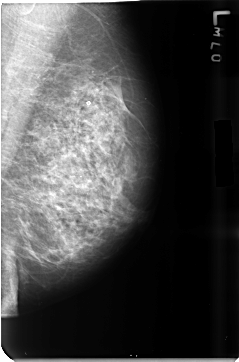

B_3500_1.RIGHT_MLO

RIGHT_MLO LINES 4640 PIXELS_PER_LINE 3152 BITS_PER_PIXEL 12 RESOLUTION 50 NON_OVERLAY